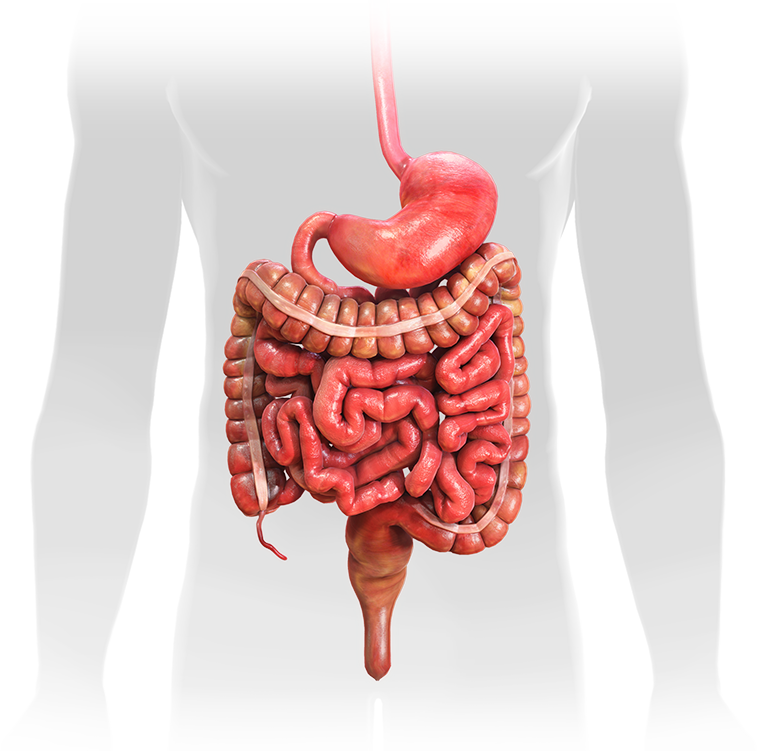

Анатомия желудка и сердца: визуализация и изучение